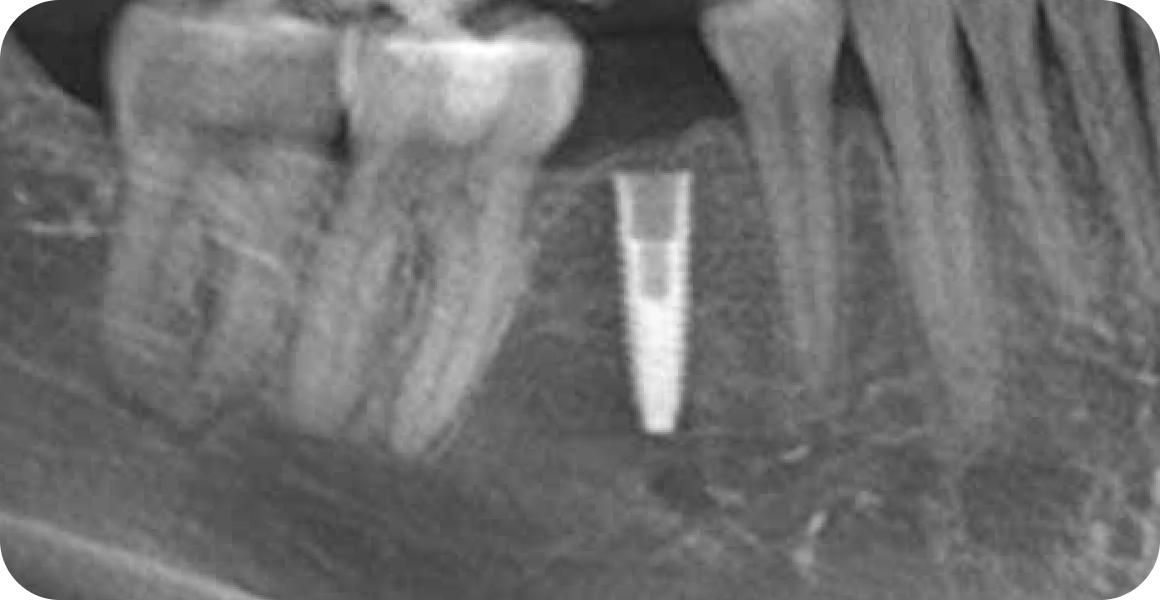

Установка импланта

Первый этап:

установка импланта в кость

Операция проходит

под местной анестезией

Длительность: 30-60 мин

Следующие 3-4 месяца идет период приживления импланта к кости

Если была костная пластика, то 6 месяцев, а сам имплант находится под десной и его не видно